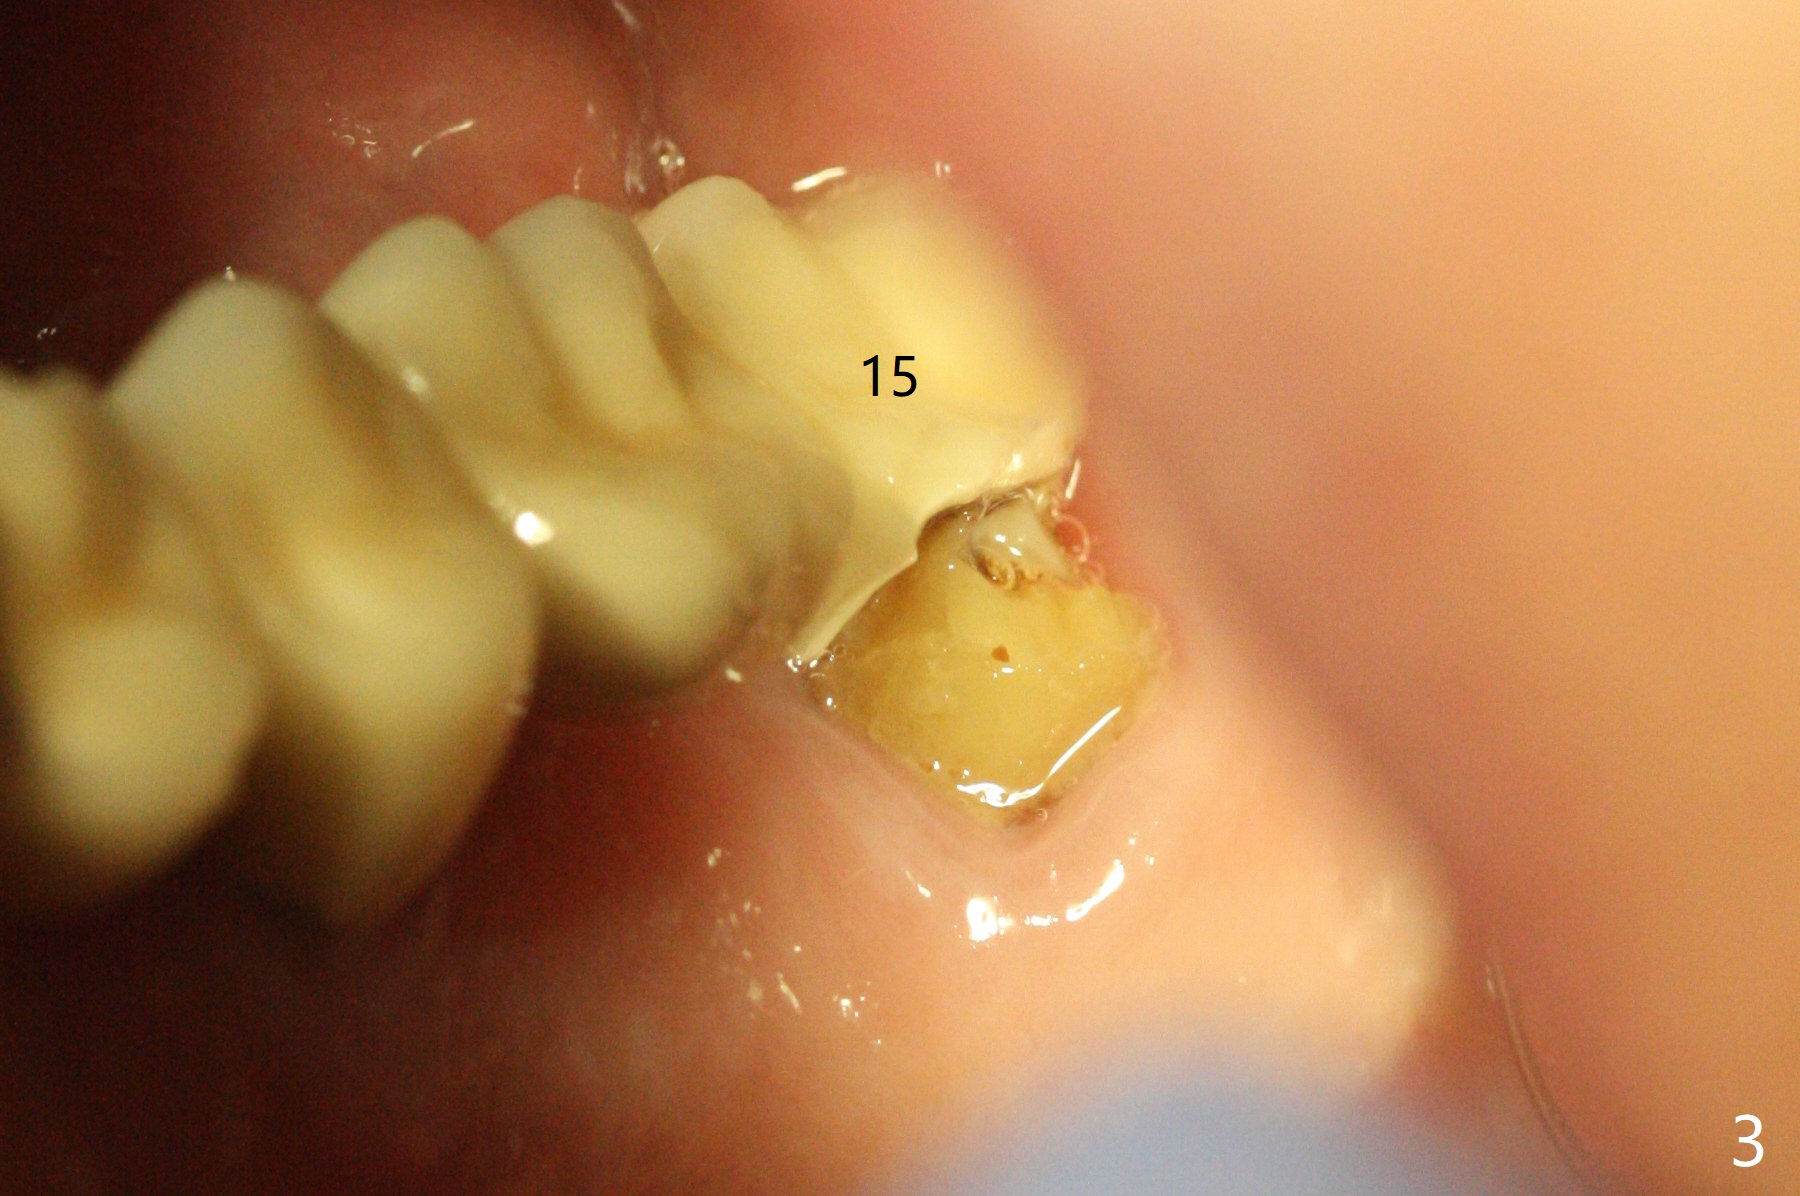

A 55-year-old woman is a bruxer (Fig.1). In 5 years the upper left FPD is fractured between #11 and 12 (Fig.2) and at #15 (Fig.3). Sectioning the FPD shows #15 non-salvageable (Fig.4). Implants will be placed at #12, 14 and 15. Sinus lift seems necessary at #14 (4 mm).